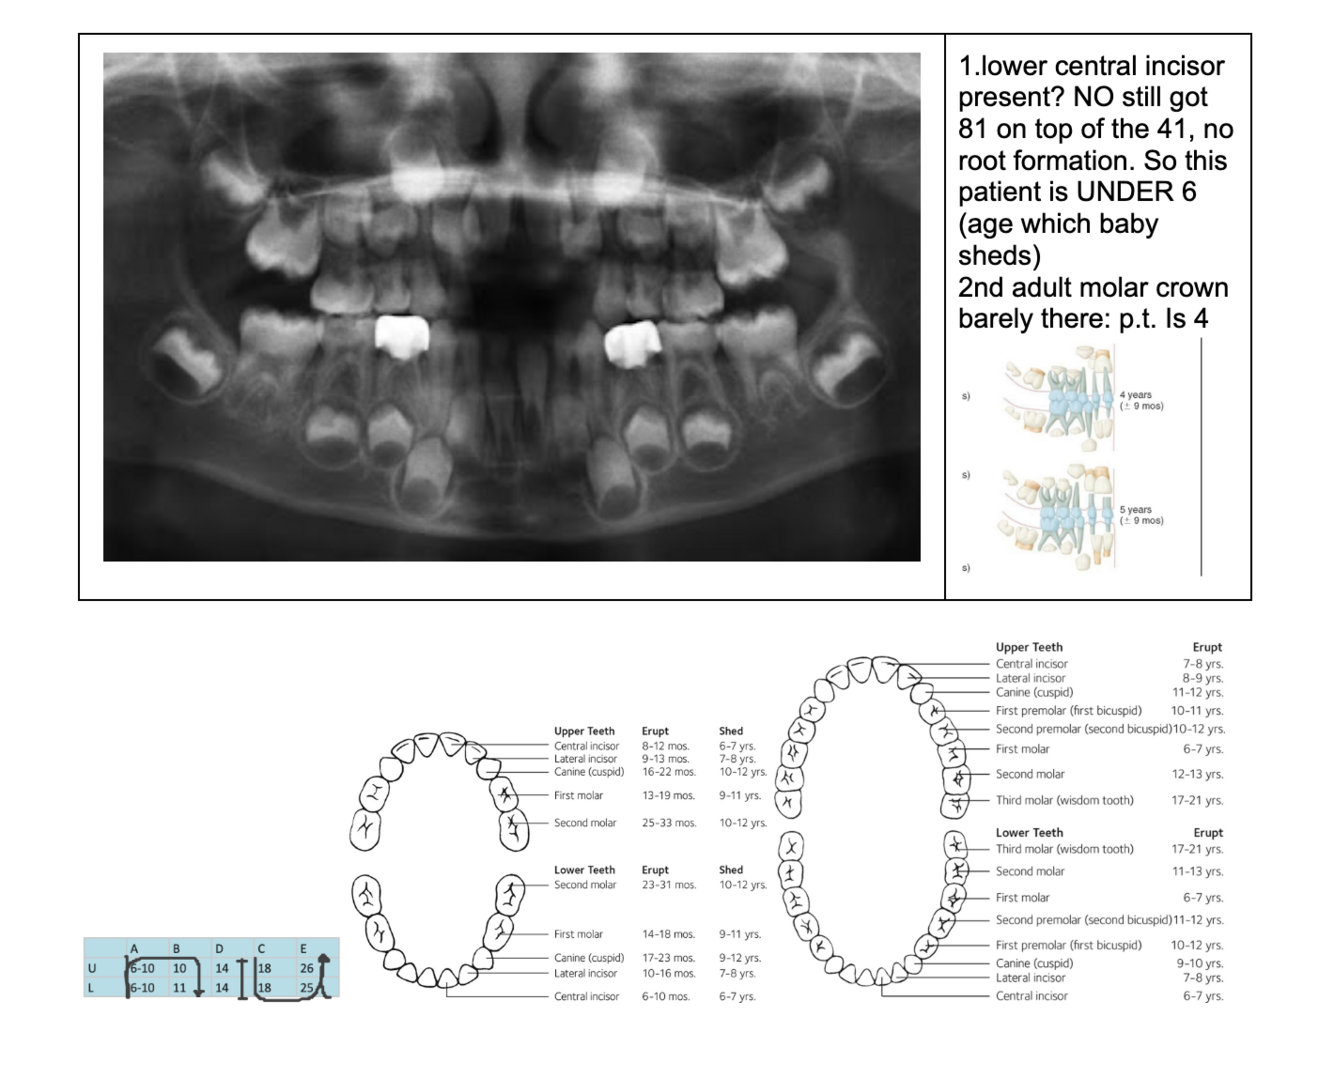

Permanent lower incisors present? Yes, so definitely 6-7

Permanent upper Incisors not erupted yet. Therefore not 7-8 y.o.

Conclusion = 6 y.o